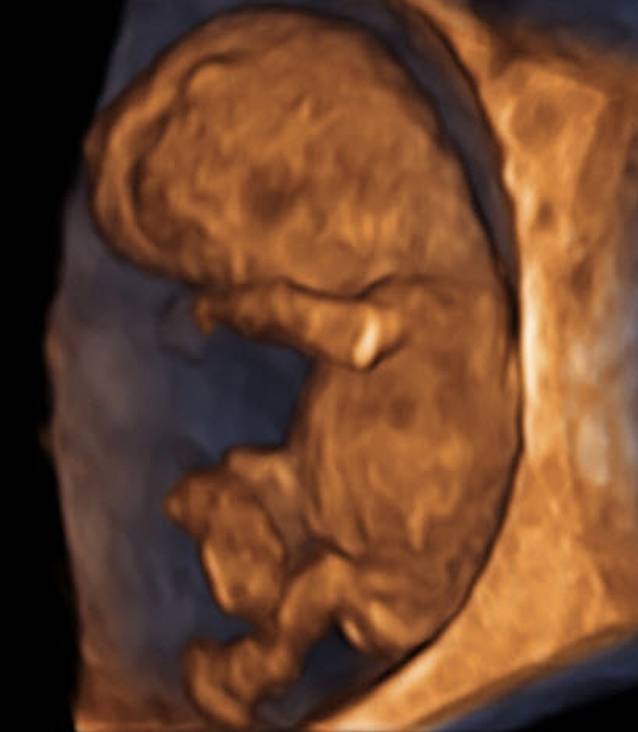

Abb. 3

30 mm CRL – hier liegen Robinson, Pexsters und Hadlock alle bei 9 + 5 SSW

Ein 3‑D-Schall ist schön, die darin abgegriffenen Messstrecken sind allerdings wesentlich ungenauer als die von B‑Mode-Aufnahmen (Abb. 3 und 4).

Selber Embryo wie in Abb. 4 im Zuge derselben Untersuchung. 3‑D ist optisch wesentlich anschaulicher als B‑Mode, allerdings bei Einbringen der Messstrecken wesentlich ungenauer